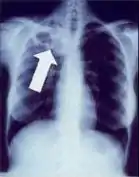

Chest x-ray of Ghon's complex of active tuberculosis

2. Any cavitary lesion - Lucency (darkened area) within the lung parenchyma, with or without irregular margins that might be surrounded by an area of airspace consolidation or infiltrates, or by nodular or fibrotic (reticular) densities, or both. The walls surrounding the lucent area can be thick or thin. Calcification can exist around a cavity.